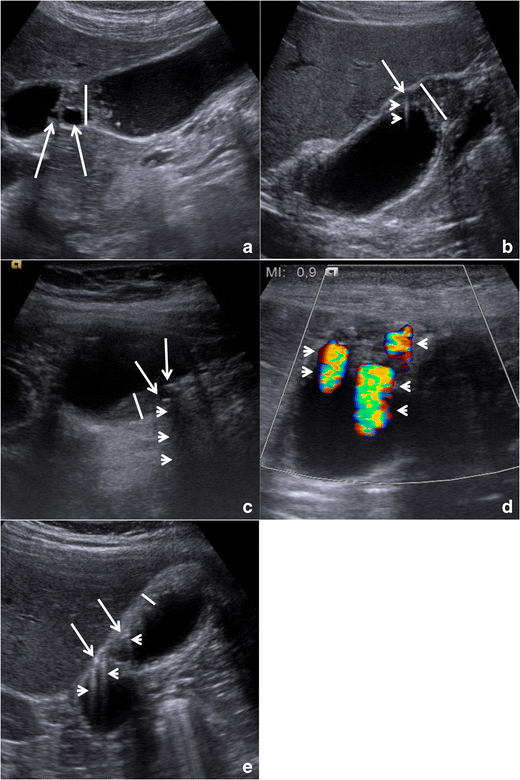

Fig. 5

Gallbladder adenomyomatosis: typical US findings in annular type (a), fundal type (b and d), segmental type (c) and diffuse type (e). Gallbladder wall thickening (line) is always seen in gallbladder adenomyomatosis, but it is non-specific. On b-mode images, Rokitansky–Aschoff sinuses (arrows) typically appear anechoic (a), but they can also appear hyperechoic if cholesterine crystals or calcifications are present (b and c). Comet-tail reverberation artefacts (Figures b and e, arrowheads) or acoustic shadowing (c, arrowheads) are usually observed profoundly in RAS. On colour Doppler images (d), twinkling artefacts (arrowheads) may be observed profoundly in RAS

Small anechoic cystic spaces (1 – 10 mm) representing clear bile-filled RAS should be recognized within the thickened gallbladder, being pathognomonic for GA (Fig. 5a). Whenever cholesterine crystals fill RAS, they appear as intramural echogenic spots in association with reverberation artefacts (Fig. 5b and e). Reverberation artefacts are the consequence of the coexistence of different acoustic impedance media, i.e., clear bile and cholesterine crystals, within RAS and appear as hyperechoic “comet-tail” artefacts that project deeply into RAS. Sometimes RAS themselves may be not directly recognizable at the origin of reverberation artefacts. Calcification-filled RAS appear as intramural echogenic spots associated with posterior acoustic shadowing (Fig. 5c). Also, the presence of cholesterine crystal- or calcification-filled RAS is virtually diagnostic for GA.

Twinkling artefacts on colour Doppler ultrasound (Fig. 5d) are due to the interaction of the ultrasound beam with a rough acoustic interface composed by randomly disposed strongly reflecting media (i.e., cholesterine crystals or calcifications) [22]. Twinkling artefacts appear as rapidly alternating red and blue colour Doppler signals, “comet-tail” shaped, deeply in RAS, and are better appreciable using low-frequency probes [23]. Their presence is strongly associated with GA.